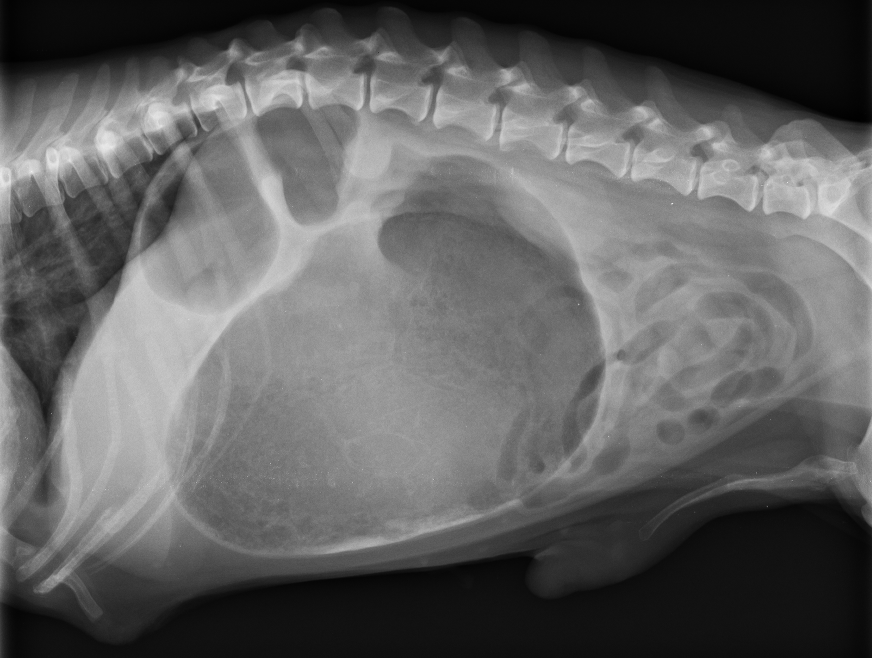

X光下顯示脹大、扭轉的胃

11歲的已絕育臘腸母狗米奇,晚上吃完飯後突乾嘔、喘 、哀嚎、肚子脹大,經影像檢查診斷為胃擴張扭轉 Gastric dilatation-volvulus(GDV) 。